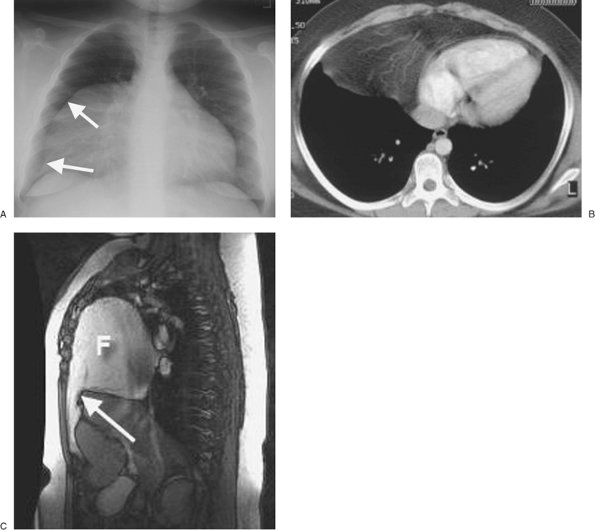

FIGURE 9-41. Foramen of Morgagni hernia. A: PA chest radiograph of an 11-year-old girl shows an abnormal right mediastinal contour (arrows) and loss of the normal right heart border. B: CT shows fat and prominent omental vascular structures anterior to the heart. C: Sagittal T1-weighted magnetic resonance image shows a defect in the anterior diaphragm (arrow) and herniation of high-signal fat (F) into the anterior chest.